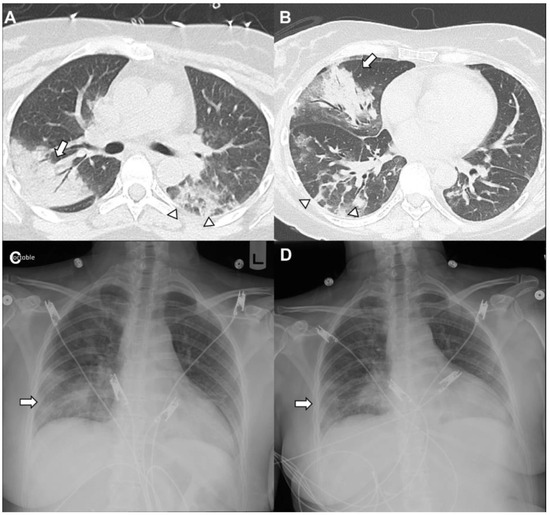

Pulmonary Complications of Cancer Therapy: Clinical Presentations, Imaging Patterns, and Management Strategies

by Bilal Zafar, Tasmea Haque, Miranda Tan, Ritika Singh, Lara Bashoura, Ajay Sheshadri, Maria Azhar and Saadia A. Faiz

Background and objectives: Therapeutic agents for cancer can cause unique pulmonary toxicities and mimic other conditions. The advent of new targeted molecular and immune therapies has changed the landscape of cancer treatment. These adverse events pose diagnostic and therapeutic challenges. This review aims to summarize the clinical presentations, radiographic patterns, and management strategies for noninfectious pulmonary complications associated with cancer therapies. Materials and methods: A literature review was conducted focusing on drug-induced lung injury (DILI), radiation-induced lung injury (RILI), pleural disease, pulmonary vascular complications, and other inflammatory conditions in patients with cancer. The data sources included clinical trials, guideline recommendations, observational studies, and expert consensus addressing incidence, pathophysiology, imaging findings, and treatment approaches. Results: Noninfectious pulmonary sequelae of anti-neoplastic therapies encompass a broad spectrum of etiologies. DILI occurs in up to 30% with variable onset and severity. The patterns can be diverse but include interstitial pneumonitis, organizing pneumonia, and diffuse alveolar damage. RILI is common and influenced by the radiation dose, volume, and concurrent therapies, and it may have both acute and chronic clinical and radiographic presentations. Pleural disease may arise from radiation and other agents, and the determination of etiology can impact management. Pulmonary vascular disease arises from many different etiologies, including therapies such as tyrosine kinase inhibitors and proteosome inhibitors, thromboembolic disease, as well as rare processes, including pulmonary veno-occlusive disease. Other conditions such as transfusion-related lung injury, cryptogenic organizing pneumonia, and interstitial lung abnormalities can also further complicate the diagnosis. Conclusions: Noninfectious pulmonary complications related to cancer therapies are diverse and often indistinguishable from infectious or malignant processes. The integration of clinical history, imaging, and selective invasive testing are needed for a timely diagnosis. Management typically involves withdrawal of the offending agent and corticosteroids, with immunosuppressive therapy reserved for severe or refractory cases. The awareness of these entities and early recognition are critical to optimizing outcomes. Full article

(This article belongs to the Section Pulmonology)